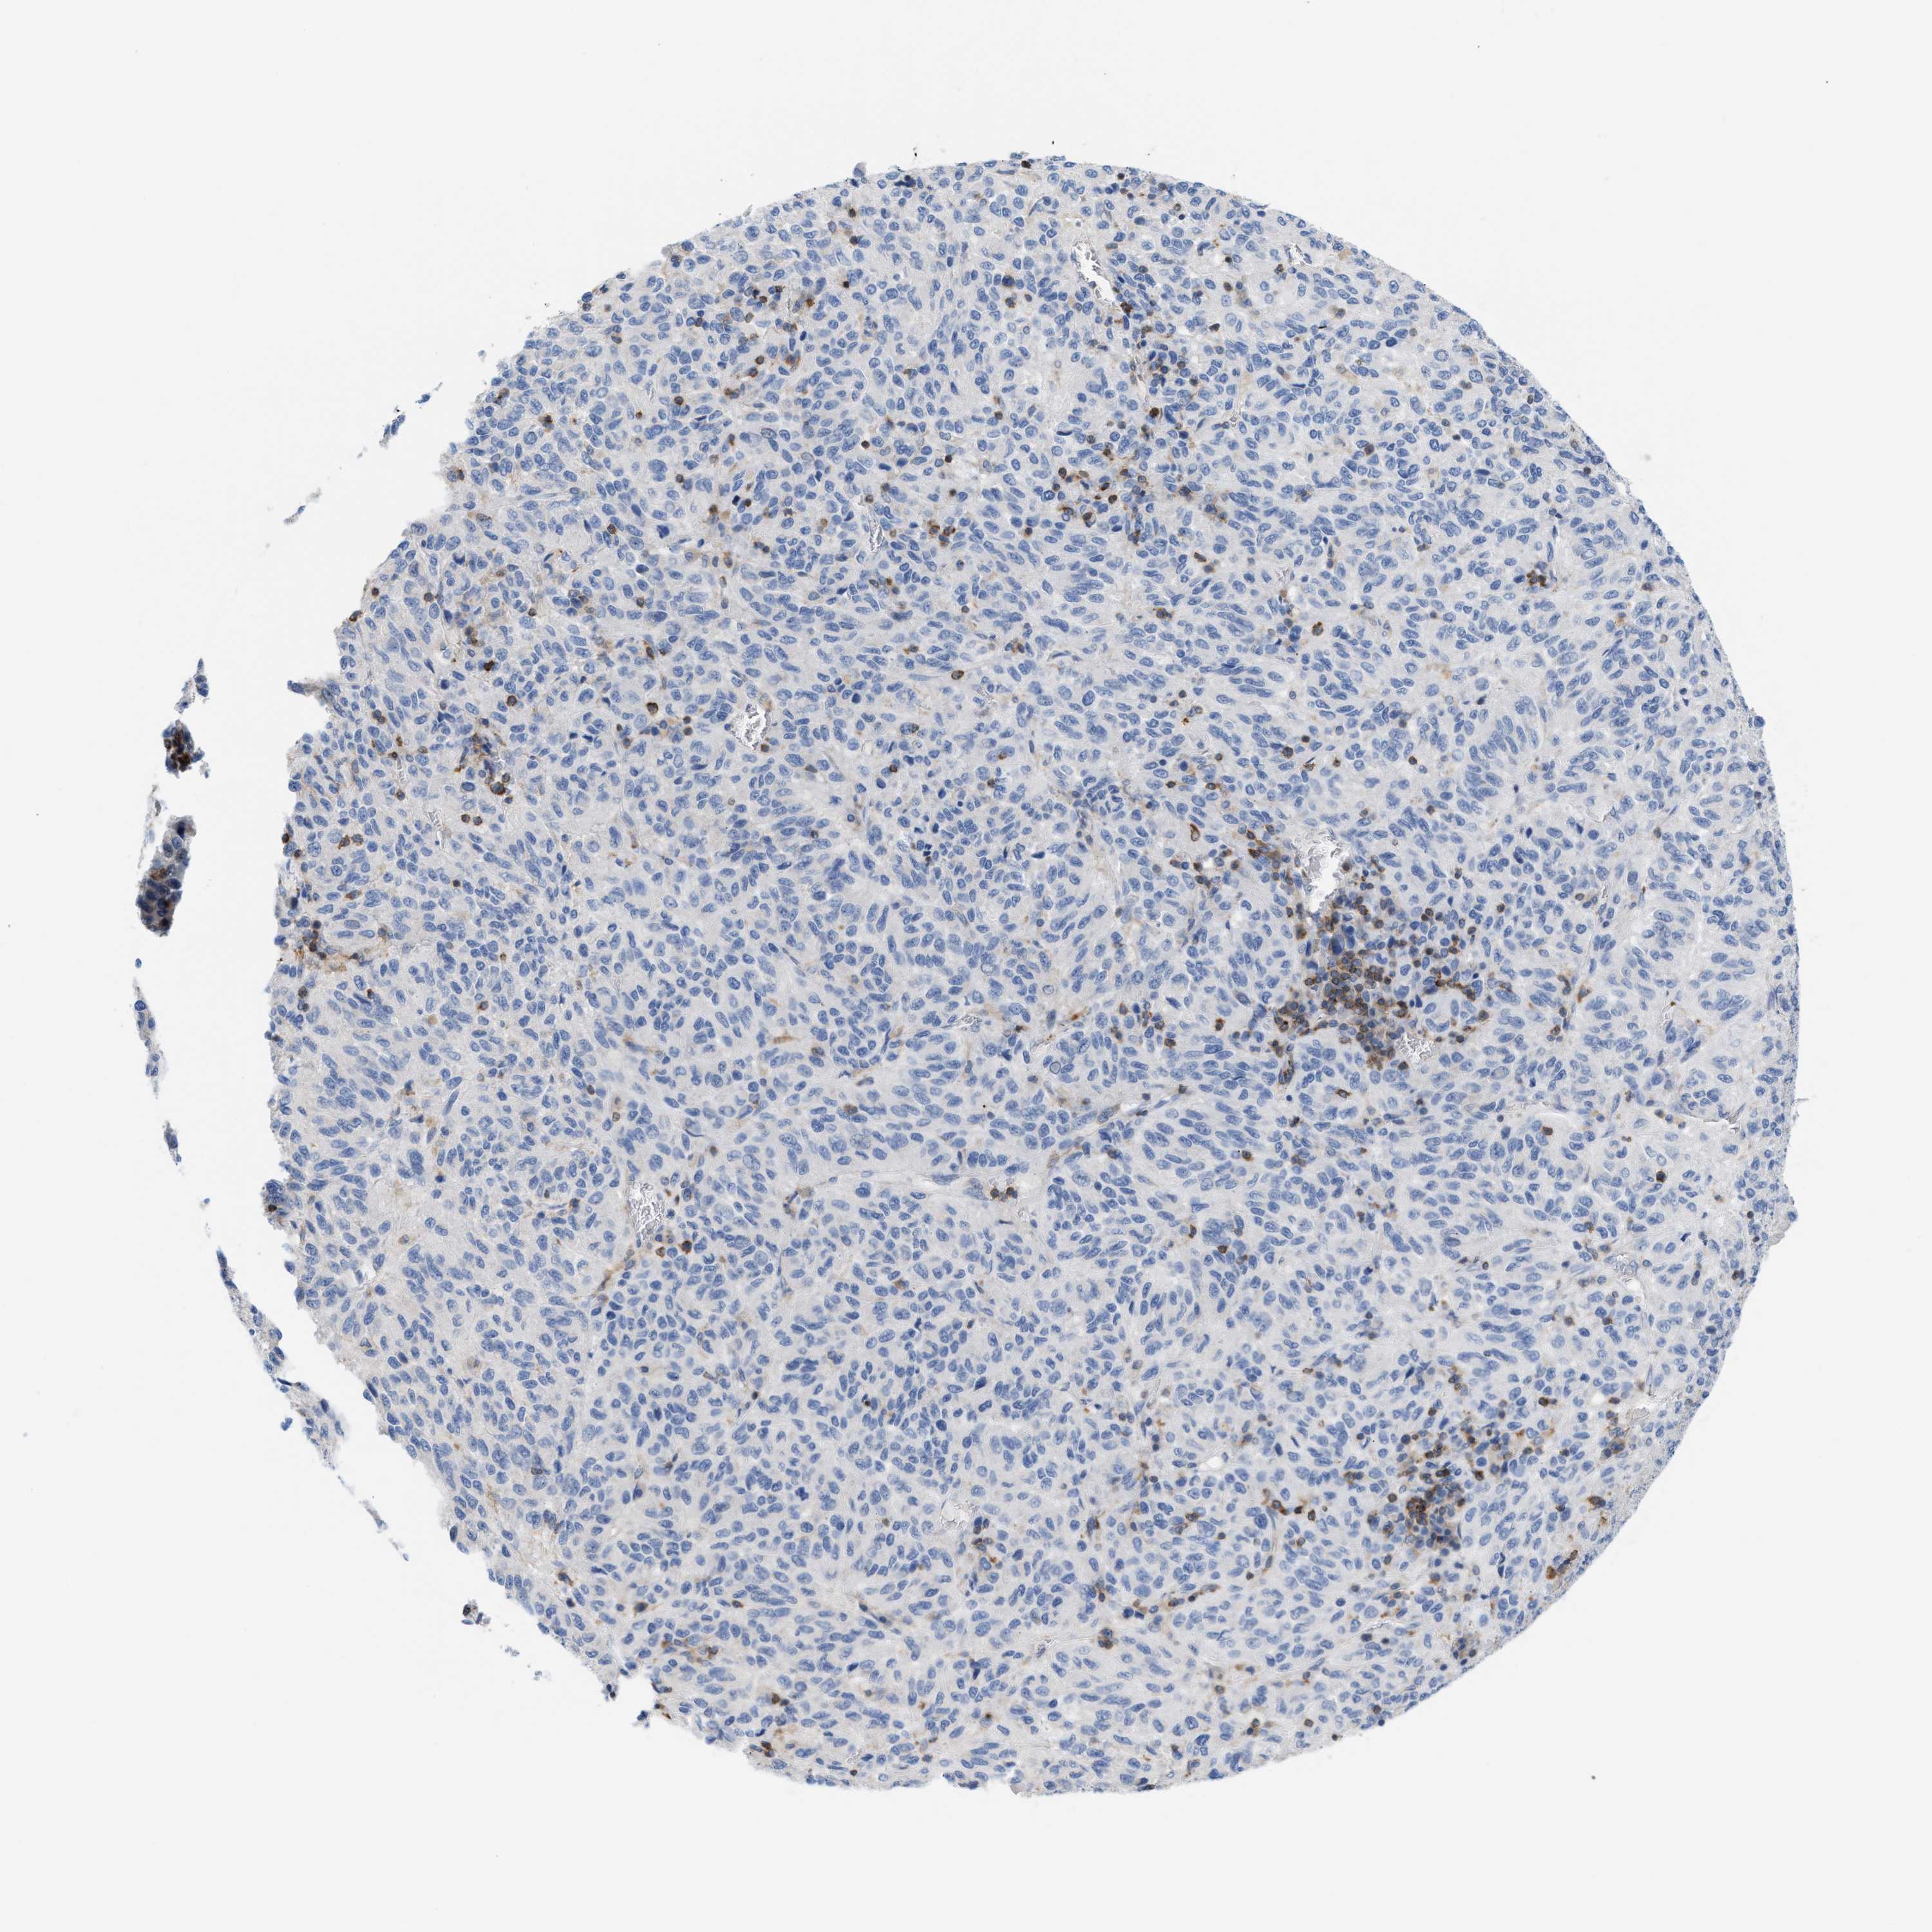

MELANOMA - Protein expressioni

A mouse-over function shows sample information and annotation data. Click on an image to view it in a full screen mode. Samples can be filtered based on level of antibody staining by selecting one or several of the following categories: high, medium, low and not detected. The assay and annotation is described here.

Note that samples used for immunohistochemistry by the Human Protein Atlas do not correspond to samples in the TCGA dataset.

Antibody stainingi

Antibody staining in the annotated cell types in the current human tissue is reported as not detected, low, medium, or high, based on conventional immunohistochemistry profiling in selected tissues. This score is based on the combination of the staining intensity and fraction of stained cells.

Each image is clickable and will lead to virtual microscopy that enables deeper exploration of all samples and also displays staining intensity scores, fraction scores and subcellular localization as well as patient and tissue information for each sample.

Antibody HPA018467

Antibody CAB005247

Staining

High

Medium

Low

Not detected

Intensity

Strong

Moderate

Weak

Negative

Quantity

>75%

75%-25%

<25%

None

Location

Nuclear

Cytoplasmic/membranous

Cytoplasmic/membranous,nuclear

Malignant melanoma, NOS

Malignant melanoma, Metastatic site